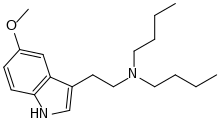

Substituted tryptamines, or serotonin analogues, are organic compounds which may be thought of as being derived from tryptamine itself. The molecular structures of all tryptamines contain an indole ring, joined to an amino (NH2) group via an ethyl (−CH2–CH2−) sidechain. In substituted tryptamines, the indole ring, sidechain, and/or amino group are modified by substituting another group for one of the hydrogen (H) atoms.

| DBT | artificial | H | (CH2)3CH3 | (CH2)3CH3 | N,N-dibutyltryptamine | 15741-77-2 |